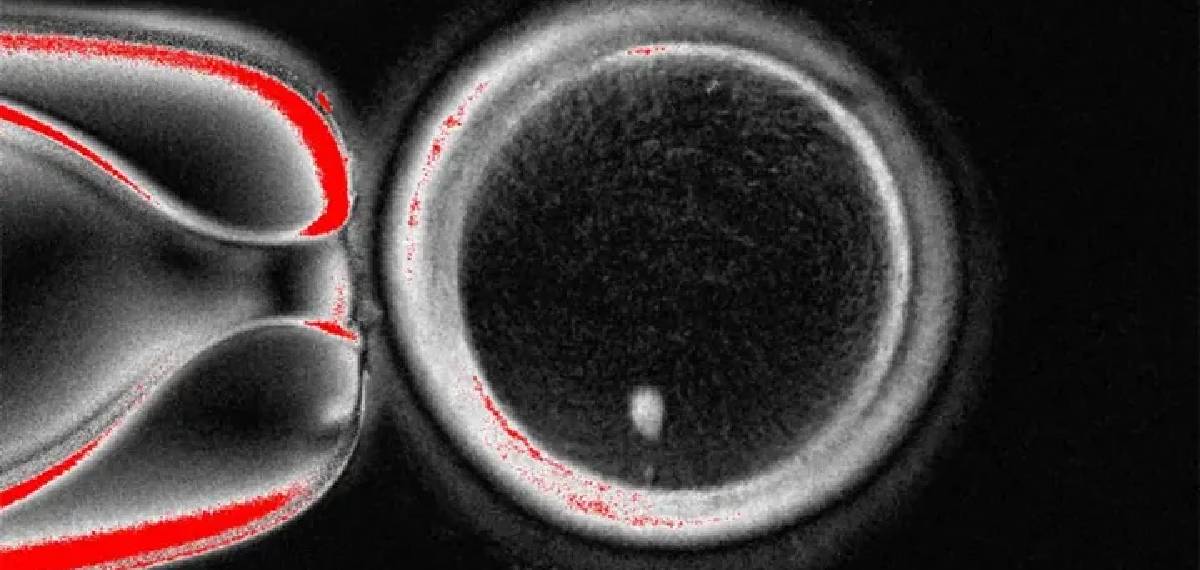

ഈ പ്രക്രിയയിലെ ഏറ്റവും നിര്ണ്ണായകമായ ഘട്ടം ബീജ സങ്കലനത്തിന് 23 ക്രോമസോമുകളുളള ഒരു അണ്ഡം 23 ക്രോമസോമുകള് വഹിക്കുന്ന മറ്റൊരു ബീജവുമായി സംയോജിപ്പിക്കുന്നതാണ്. ഈ രീതി ഉപയോഗിച്ച് ഗവേഷകര് 82 ഫങ്ഷണല് ഓസൈറ്റുകള്(അണ്ഡങ്ങള്) ഉത്പാദിപ്പിക്കുകയും ബീജം ഉപയോഗിച്ച് അവയെ ബീജ സങ്കലനം ചെയ്യുകയും ചെയ്തു. ആറാം ദിവസത്തോടെ ഒന്പത് ശതമാനം ഭ്രൂണവികാസം സംഭവിക്കുകയായിരുന്നു. ഈ പഠനം ശൈശവ ദിശയിലാണ്. ആളുകളില് സുരക്ഷിതവും ഫലപ്രദവുമാകുമോ എന്ന് സ്ഥാപിച്ചെടുക്കാന് വര്ഷങ്ങളുടെ ഗവേഷണം ആവശ്യമാണെന്നും ഗവേഷകര് പറയുന്നുണ്ട്.